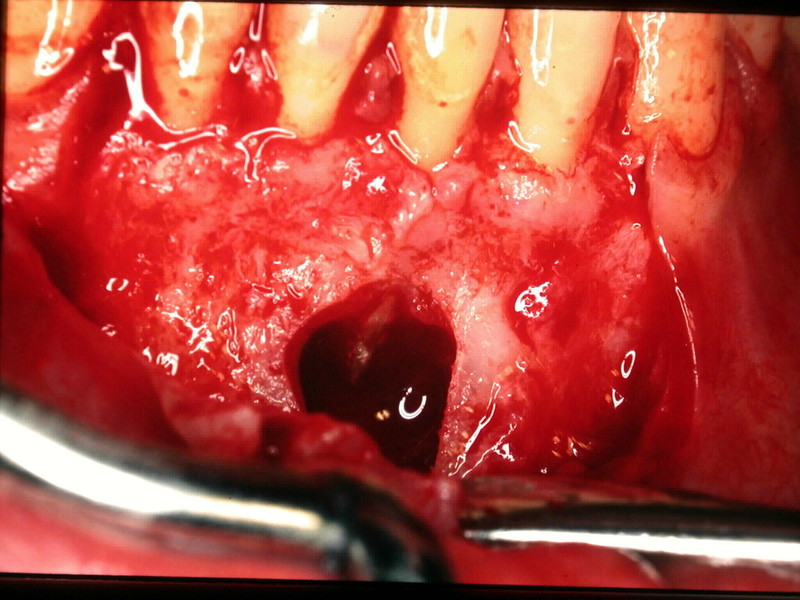

CHIRURGIA ORALE

ABBIAMO SEMPRE ESEGUITO CON SUCCESSO TUTTI GLI INTERVENTI DI CHIRURGIA ORALE COME LE ESTRAZIONI COMPLESSE DI DENTI DEL GIUDIZIO INCLUSI, LE GERMECTOMIE DEGLI 8°, LE APICECTOMIE, L' ASPORTAZIONE DI CISTI ENDOOSSEE, LE OSTEOPLASTICHE PREPROTESICHE, GLI INNESTI DI OSSO AUTOLOGO O ETEROLOGO AI FINI IMPLANTARI O PREPROTESICI, I GRANDI E PICCOLI RIALZI DI SENO MASCELLARE E TUTTA LA SERIE DI INTERVENTI DI CHIRURGIA GENGIVALE E MUCOGENGIVALE.